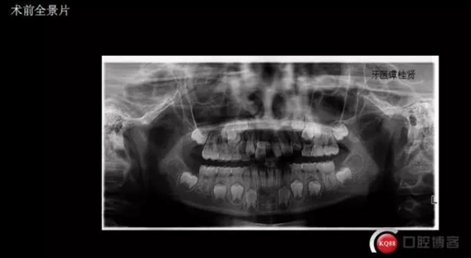

三年半前,家長領(lǐng)著小孩前來要求矯正牙齒,男,約八歲,兩中切牙間隙約12MM,有一多生牙,全景片顯示深處還橫著一顆,也許正處叛逆期,小孩非常的調(diào)皮,經(jīng)過幾次的各種哄和商談,也可能為了好看,終于勉強同意先拔掉露出的多生牙,前牙片斷弓關(guān)閉間隙

拔掉一顆后大概大半年時間很快就把間隙關(guān)閉了,但是由于還有一顆橫在兩中切牙間,牙縫始終得不到完全關(guān)閉,此時只能拔掉深部埋伏阻生的牙才能進一步矯正治療,但小孩一聽又要做一次手術(shù)有不同意了,這樣又拖了兩年多,長大了一些自然懂事了些。